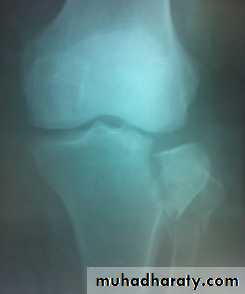

For displaced fractures

treatment is by open reduction and internal fixation with

plate and screws as it is an intra articular fracture.

fixation of tibial plateau fracture